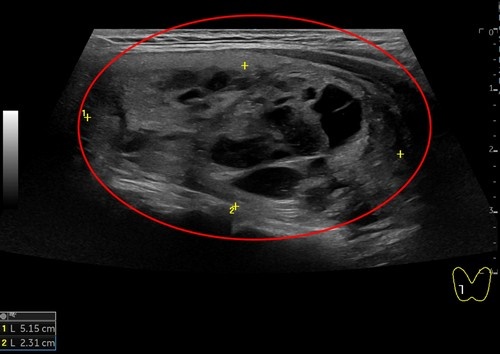

日前,一位51歲女性病人因頸部中間部位腫大來花蓮慈濟醫院影像醫學部施于泰醫師門診,經以超音波檢查,發現右邊有一5.15公分結節,另一個結節靠近甲狀腺峽部約2.99公分;在以細胞學穿刺檢查後為良性結節。病人在接受甲狀腺消融術治療後,隔天即出院恢復正常生活,且一週後已明顯消腫,無副作用發生。

左圖:這位女病患,右側5.15公分結節微波消融前,超音波影像。(施于泰提供)